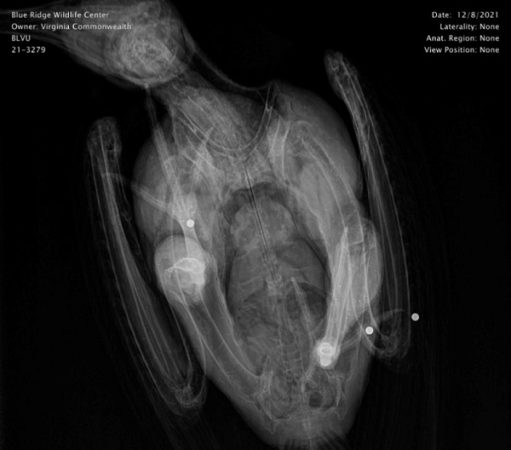

This patient was rescued on December 8th with the help of Loudoun County Animal Services and Kristi’s Caring Hands Wildlife Rehabilitation and Education after being hit by a car. They noted that the vulture was found near a dead deer. Upon admission, radiographs also revealed pellets from a gunshot.

This crime has been reported to our state wildlife agency and US Fish and Wildlife Service for further investigation.